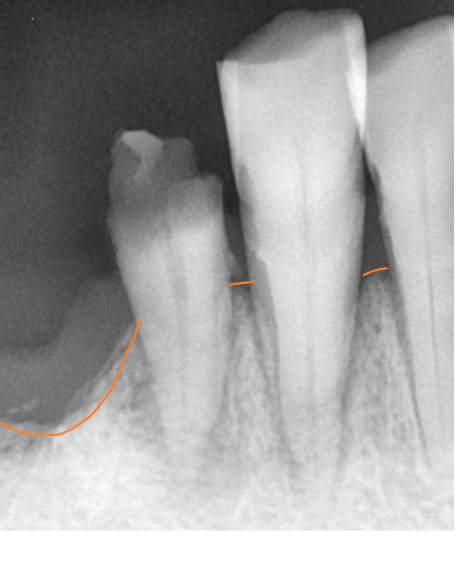

작은 x ray도 찍어보고

ct도 찍어 찍어 최대한 남길 수 있는 치아들은 남기고 싶었으나

아래 치아의 경우 몹시도 흔들리고 충치가 심하여

남아있는 치아 전부 제거가 필요했습니다.